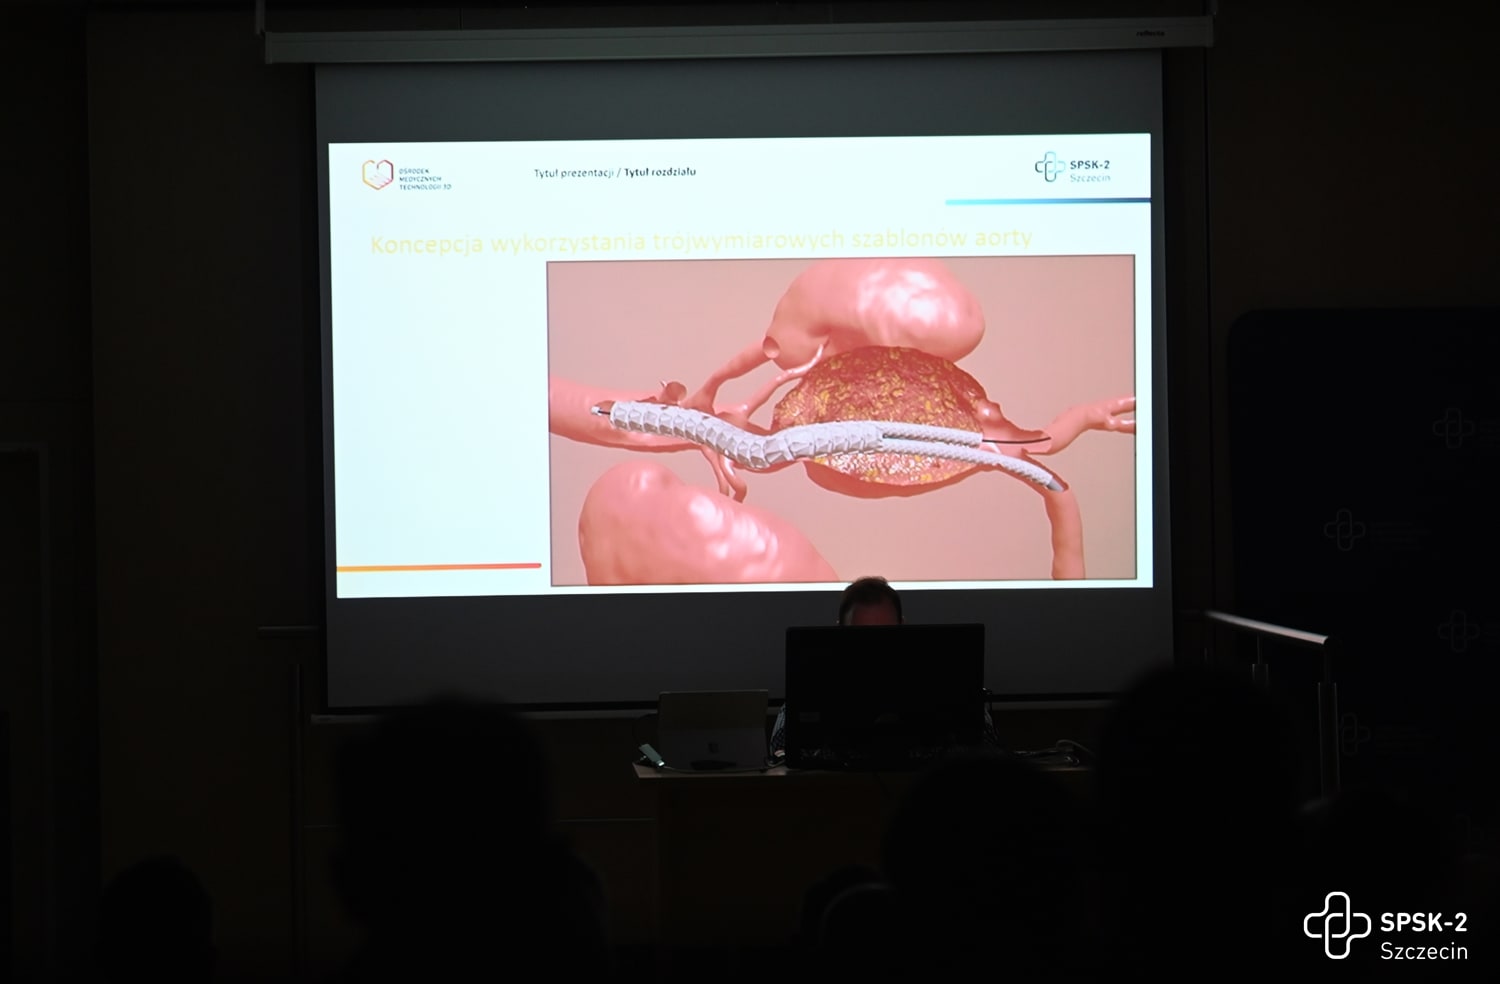

2022-11-07Lekarze Kliniki Chirurgii Naczyniowej, Ogólnej i Angiologii naszego szpitala dokonali pierwszego w kraju, całkowicie przezskórnego wszczepienia modyfikowanego stent-graftu. Była to operacja ratująca życie, a pomocna przy tym - technika druku 3D.

Dostępy całkowicie przezskórne (bez cięcia skóry) wykonuje tylko kilka ośrodków w Polsce i jest to metoda coraz częściej preferowana, ale głównie do mniej skomplikowanych przypadków. Tym razem do szpitala na Pomorzanach trafił 75-letni pacjent z objawowym tętniakiem okołotrzewnym (aorty piersiowo-brzusznej) - bolesnym, grożącym pęknięciem, a zatem stanowiącym zagrożenie życia. Dodatkowo chory nie miał szans na skorzystanie ze standardowego stent-graftu branchowego (z doszywanymi „rękawkami” na naczynia) czy fenestrowanego (z wyciętymi „okienkami” na naczynia) zamawianego u producenta z powodu występujących u niego dodatkowych naczyń, odchodzących od aorty (osobne ujście tętnicy wątrobowej). Nie mógł też czekać na wyprodukowanie stent-graftu szytego dla niego na miarę, bo trwałoby to 8-12 tygodni, a bolesność tętnika świadczyła, że rychło pęknie. Groziło to śmiercią pacjenta.

Leczenie stent-graftami modyfikowanymi jest w domeną naszych lekarzy Kliniki Chirurgii Naczyniowej, Ogólnej i Angiologii, którzy wypracowali wysokiej jakości standard postępowania w użyciu tej metody. Wykorzystując model aorty danego pacjenta, wydrukowany techniką 3D, modyfikują własnoręcznie, już na sali operacyjnej standardowe stent-grafty i dopasowują je indywidualnie do anatomii operowanego pacjenta. Po co? Bo mimo ogólnej takiej samej budowy każdego z nas, układ naczyń krwionośnych, ich budowa, odległości między poszczególnymi naczyniami różnią się u każdego człowieka. Dlatego dla efektywności działania wszczepianego, standardowego stent-graftu – proteza ta powinna być dopasowana do budowy chorego. Chirurdzy naczyniowi USK-2 są jedynym zespołem w Polsce, który tego typu zabiegi wykonuje rutynowo, również w przypadkach nagłych. Jednak taki sposób leczenia, jak i wszelkie inne zaawansowane procedury aortalne, wymaga licznych, często trudnych dostępów naczyniowych (np. nacięć w pachwinach, rękach i klatce piersiowej) – tj. cięć i operowania „na otwarto”. Dla chirurga taka operacja jest łatwiejsza, bo pole operacyjne jest widoczne jak na dłoni. Ale dla pacjenta dochodzenia do formy po takiej operacji jest długotrwałe, bolesne i mało komfortowe. Dlatego użycie przez szczecińskich lekarzy wyłącznie dostępu przezskórnego (bez cięcia) w leczeniu tętnika jest dużym krokiem na przód w chirurgii naczyniowej, a fakt, że to pierwszy tego typu zabieg w Polsce to ogromny sukces naszych „naczyniowców” i świadczy o ich doskonałej technice operowania.

Tłumacząc obrazowo - tętniakiem aorty nazywany nadmierne (o ponad 50%) poszerzenie aorty, która jest największą tętnicą w ciele człowieka. Może ono występować na każdym jej odcinku, ale najczęściej występuje w części brzusznej. Przyczyną ich powstania jest odkładanie się blaszek miażdżycowych, nadciśnienie tętnicze, nadmierny, gwałtowny wysiłek czy uraz, czasem także wrodzone nieprawidłowości w budowie naczynia. Ryzyko wystąpienie tętniaka aorty brzusznej wzrasta z wiekiem i jest szczególnie wysokie u mężczyzn około 65. roku życia. Szczególnie niebezpieczne są tętniaki bezobjawowe, które w każdej chwili mogą grozić pęknięciem i prowadzić do zgonu chorego.

W Ośrodku Medycznych Technologii 3D (OMT3D) powstać będą trójwymiarowe modele organów pacjentów – prawidłowe lub ze zmianami patologicznymi. Wydruk będzie powstawał w najnowszej generacji drukarkach 3D, umożliwiających druk nie tylko dowolnych struktur anatomicznych pacjenta z ich patologiami, ale odwzorowujących także kolory, strukturę, giętkość i twardość prawdziwych organów i tkanek. A dzięki goglom Hololens2, operujący lekarz będzie w powietrzu nawigował hologramem, przedstawiającym zdjęcia diagnostyki obrazowej pacjenta.